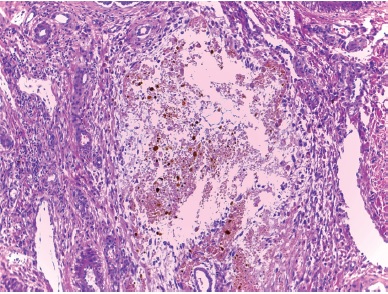

El examen del hígado mostró un cuadro mixto de cirrosis obstructiva con colestasis acentuada y una fibrosis de bandas gruesas y limpias, con hiperplasia hamartomatosa de conductos (Figura 3) con un patrón que recordaba a la fibrosis hepática congénita; condición, sin embargo, en la que no suele haber colestasis ni insuficiencia hepática. El fragmento de hígado resecado no incluyó el hilio pero en uno de los cortes se apreció un conducto biliar mayor dilatado y sin epitelio pero con contenido biliar (Figura 4). Este se encontró en un espacio porta mayor y nos sugirió la posibilidad de una enfermedad de Caroli, que sería una malformación de la placa ductal con colestasis.1-3 Como existió evidencia de que no hubo obstrucción biliar extrahepática –la vesícula presente y las heces estuvieron pigmentadas– este caso pareció corresponder a una malformación de la placa ductal con componentes de enfermedad de Caroli y de fibrosis hepática congénita; para esta combinación de dos expresiones de malformación de la placa ductal se ha propuesto el nombre de síndrome de Caroli.4 Los espacios porta periféricos mostraron colestasis acentuada con cambios inflamatorios incipientes en colangíolos (Figura 5) y en el parénquima hepatocelular marcada colestasis y transformación de células gigantes como respuesta a la obstrucción (Figura 6). El nódulo prominente descrito sobre la superficie del hígado en el corte tuvo más o menos el mismo aspecto que el resto y probablemente fue un foco de regeneración nodular. La presencia de regeneración y los datos de obstrucción biliar nos permiten proponer un componente de cirrosis obstructiva superpuesto a la patología de base que serían la fibrosis hepática congénita y los cambios de Caroli.